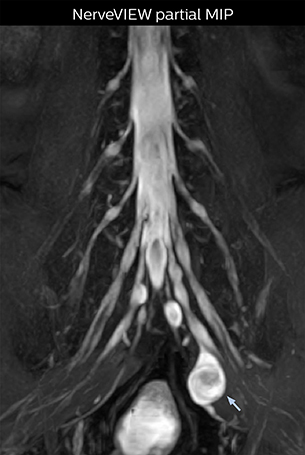

Northern Fukushima Medical Center (NFMC) Imaging Center uses the 3D NerveVIEW sequence for performing MR neurography, particularly in patients with pain and weakness in the lower limb. “It is included in about 20% of the approximately 150 lumbar spine MRI exams each month at NFMC, and can help us to determine if structures are impinging on the nerves,” says Hajime Tanji, RT, MRI technologist at NFMC.

“In such case, we would then browse through axial T2-weighted MR images slice by slice and mentally reconstruct the actual situation based on both radiculography and MRI. Fortunately, NerveVIEW can now very well show nerve courses and presence of nerve compression or edema in one single image series.” “We have often seen NerveVIEW directly depict details of the nerve compression that were not observed by radiculography. Therefore, we think that with NerveVIEW we can reduce the number of invasive examinations, especially for some patients with lumbar plexus symptoms.”

“The intra-luminal signal of veins, especially around the intervertebral space, can be suppressed well with NerveVIEW. As a result, we can easily observe the detailed nerve structure around the posterior ganglion,” he says. “This is why we use 3D NerveVIEW for intraforaminal stenosis and extraforaminal stenosis/herniation (lateral disc herniation). On the other hand, if herniation is suspected to exist inside the dorsal root ganglion (DRG), balanced TFE or ProSet-FFE is applied. NerveVIEW is not suitable for evaluating the median type of herniation.” The SE-EPI DWI-based method for MR neurography works well for large FOV exams like whole-body MRI, but focal examination of nerves is often limited by the attainable spatial resolution (both inplane and slice direction) and geometric distortion. “3D NerveVIEW achieves higher in-plane resolution – close to our other routine spine sequences – and the source images can be used instead of adding a fat-suppressed T2-weighted sequence,” Tanji says.

According to Tanji, methods such as ProSet FFE, STIR or 3D VISTA are anatomically nonselective because background signals, for instance from blood vessels, often interfere with nerves, which hampers evaluation of details, especially at the peripheral side of the nerves.